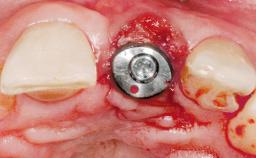

A 30-year-old female patient had lost tooth 21 and was referred to our clinic for consultation and treatment. Due to advanced apical infection, tooth 21 had been extracted two months earlier at another clinic and an acrylic-resin tooth had been bonded to the adjacent teeth. The patient desired implant treatment to avoid any damage to the adjacent natural teeth. While the patient had no history of any systemic disorder, she was a heavy smoker and exhibited medium to advanced periodontitis in the entire jaw. After the initial treatment to achieve a pocket probing depth of less than 4 mm and no bleeding on probing, a decrease in the height of the papillae mesial and distal to the extraction site and overall gingival recession were observed.

Type of Implants One-Piece|Reduced-Diameter

Placement Protocol Early or late implant placement